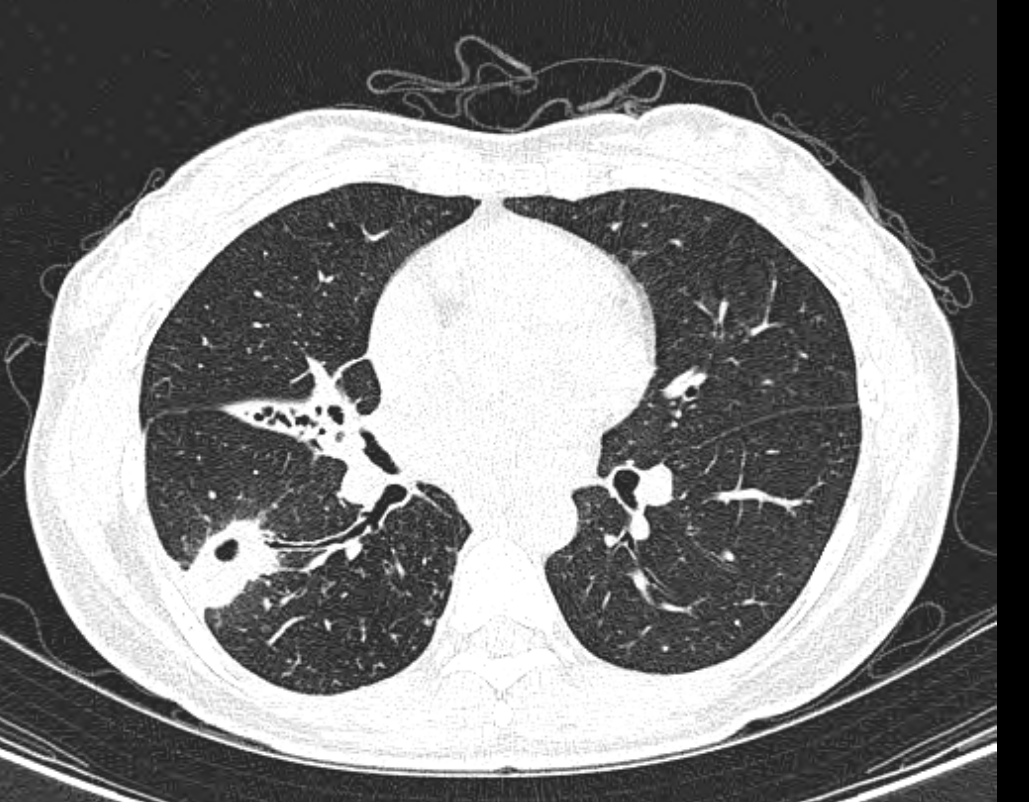

우리나라는 과거에 결핵에 걸리고도 진단이나 치료가 되지 않은 사람들이 매우 많았습니다. 따라서 결핵이 자연 치유되는 과정에서 그 흉터로 석회화가 생기는 경우가 많았습니다. 결핵은 폐에 많이 생긴다고 알려졌지만, 장이나 뼈, 간 등 모든 장기에 발생이 가능하기 때문에 간의 석회화도 그와 관련이 있을 수 있습니다.